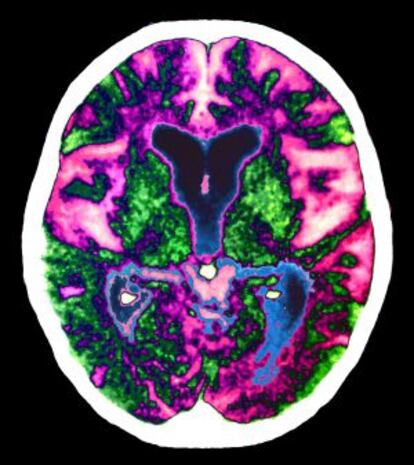

Eliminar las proteínas beta-amiloides del cerebro puede ser una manera de luchar contra el alzhéimer. Y este paso puede conseguirse –al menos en ratones- utilizando un fármaco ya conocido, el betaxoreno, según publica Science.

El estudio de la Case Western Reserve University (Claveland, Ohio) se basa en el efecto del medicamento para activar una proteína de la membrana neuronal, la apolipoproteína E, que, a su vez, ya se había visto que actúa reduciendo los acúmulos de beta-amiloide.